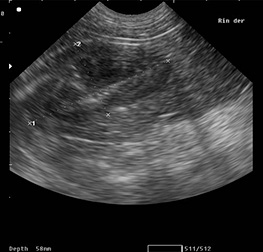

Ecografia AbdominalLa ecografía abdominal es un estudio diagnóstico que a través del uso de ondas de ultrasonido, permite observar los órganos y las estructuras que se encuentran dentro de la cavidad abdominal. También permite examinar el flujo dentro de los vasos sanguíneos a través de una ecografía especial llamada ecografía-doppler.

El estudio se realiza con un ecógrafo que emite ondas de ultrasonido a través de un transductor, que se mueve sobre la piel, por encima de los órganos que nos interesen estudiar. Las ondas se transmiten por el interior del cuerpo y al rebotar crean unas ondas que son distintas según la densidad de los tejido que atraviesan. Estas ondas son recogidas por el transductor y, a través de un ordenador, se generan imágenes de la zona que estamos estudiando.

La ecografía abdominal permite observar los órganos abdominales como el hígado, la vesícula biliar, el páncreas, el bazo, los riñones, la vejiga, tracto gastrointestinal y demás estructuras presentes. También permite ver arterias/venas y detectar la presencia de líquido entre los distintos órganos. En las hembras permite ver los ovarios, el útero y la gestación en sus diferentes estadios, mientras que en los machos se puede observar la próstata y los testículos.

Realizar la ecografía, consiste en pasar el transductor sobre la piel, en las regiones del cuerpo a evaluar; esto no provoca dolor ni irritación.